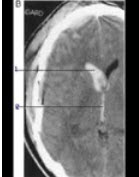

如图箭头所示出血部位为1____________2___________。